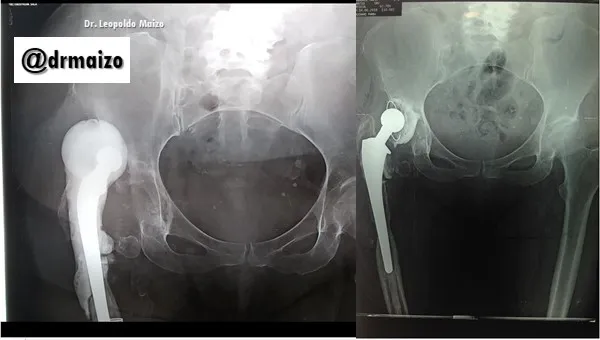

Dislocation of the hip prosthesis

We are talking about a dislocation of the hip prosthesis when the artificial femoral head comes out of the prosthetic acetabulum. Functional disability, pain and shortening of the lower limb are the main manifestations of dislocation of the prosthetic femoral head.

Radiological diagnosis is obvious most of the time and easy to detect.

Once a dislocation occurs, it must be treated with the greatest urgency and this is done with two types of techniques. One of them, called closed reduction, consists of administering the patient anesthesia (general or regional) and performing a series of maneuvers with traction of the affected limb, and put it back in place without the need for surgery.

Dr. Leopoldo Maizo - Orthopedic Surgeon